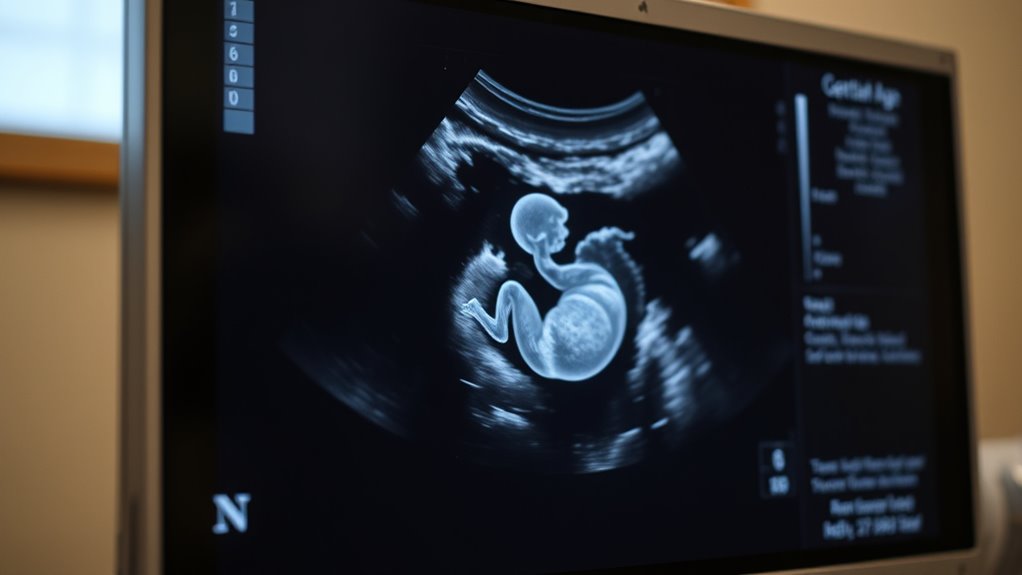

- Accurate understanding of both ages helps in proper pregnancy dating and interpretation of ultrasounds.

Understanding the difference between gestational age and fetal age is essential for accurately tracking pregnancy progress. These two terms often get used interchangeably, but they represent different timelines that can impact how you interpret your pregnancy milestones. Gestational age begins from the first day of your last menstrual period, which means it includes about two weeks before conception actually occurs. Fetal age, on the other hand, starts from the day of conception, so it’s roughly two weeks less than gestational age. Recognizing this distinction helps you and your healthcare provider better understand your pregnancy’s development and ensures more precise monitoring.

One key aspect influenced by this distinction is placental development. The placenta begins forming very early in pregnancy, around the third week after conception, and it plays a crucial role in nourishing your baby. When you think about gestational age, you’re considering the entire period during which the placenta is developing and supporting embryonic growth. This timing affects how you interpret ultrasounds and other tests, especially early on when the placenta is establishing itself. If measurements are based solely on fetal age, they might underestimate the maturity of the placenta and its ability to sustain your developing baby. Proper understanding of placental development in relation to gestational age ensures that assessments of fetal health and growth are accurate.

Embryonic growth is another critical factor impacted by the distinction. From conception to about the eighth week, your baby is in the embryonic stage, characterized by rapid development of vital organs and structures. During this period, small differences in timing can greatly influence growth assessments. Since embryonic growth occurs within a timeframe that aligns more closely with fetal age, knowing the difference allows you to interpret early ultrasound measurements correctly. If your healthcare provider is tracking growth based on fetal age, they might adjust their expectations for early development milestones, providing a clearer picture of whether your pregnancy is progressing normally. Additionally, understanding growth milestones helps in planning appropriate prenatal care and interventions. Being aware of timing differences can also help you better understand medical advice and testing schedules, reducing confusion.